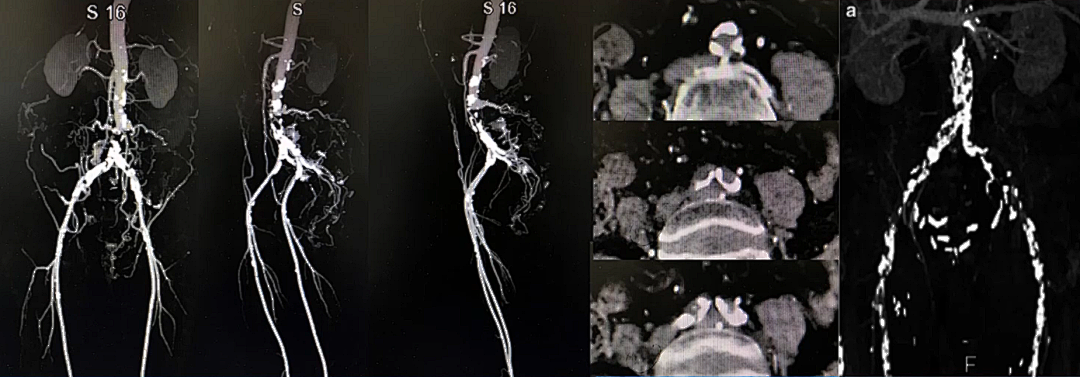

2. 钙化

主髂病变比较棘手的特点是钙化,严重钙化病变对于血管介入开通极具挑战性,为血管开通制造麻烦,增加进入内膜下风险,可能出现不可控的破裂出血,因此这些特点必须熟知和熟悉。